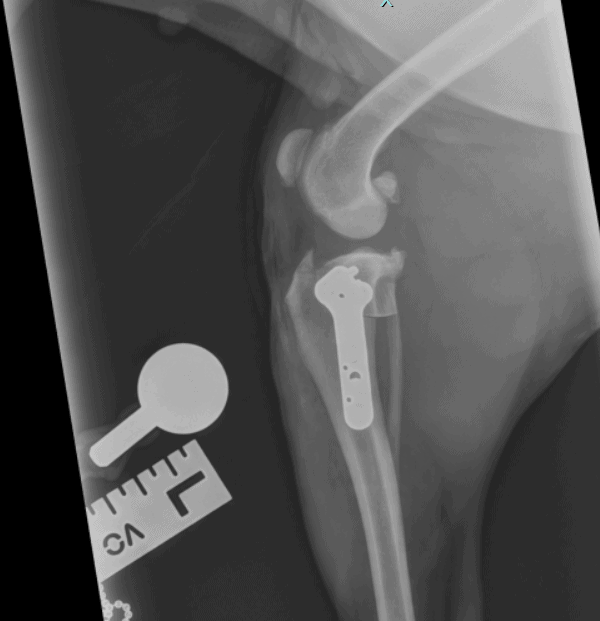

On both occasions, Betty was admitted to our hospital for x-rays, which confirmed David’s suspicions of a cruciate ligament rupture. To fix this, David performed a specialised orthopaedic surgery called a ‘tibial plateau levelling osteotomy’ – this is commonly referred to as a TPLO. During a TPLO, the tibia (the shin bone) is cut and adjusted, and a specially-engineered metal implant is inserted and fixed with screws. This changes the mechanics of the knee joint, making it more stable, so that the degenerated cruciate ligament is no longer required.

Our experienced theatre nursing team prepared and monitored Betty throughout her anaesthetic and surgery, making sure she was safe and comfortable. X-rays were taken of Betty’s leg before and after her surgery – firstly to measure her bones, to enable the correctly sized implant to be chosen, and then to ensure the implants were in the correct place. Check out the x-ray from one of Betty’s surgeries showing her new metal-work!